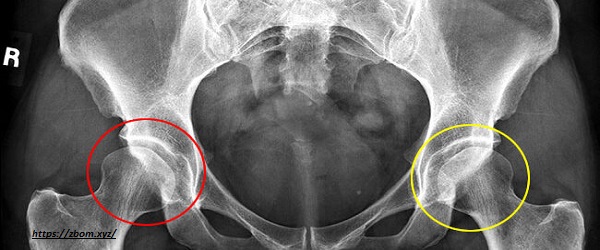

1. Hip Dysplasia

Hip dysplasia is one of the most common orthopedic conditions that affect many medium-to-large dog breeds, including Siberian huskies. It is a condition where the hip joint does not develop properly, leading to instability and eventual arthritis.